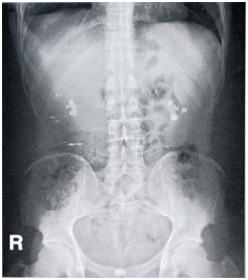

04卷-5.患者,男性,32歲,腰痛1小時(shí)入院,腹平片提示(本題滿分2.00分)

A.腎結(jié)核

B.腎結(jié)石

C.腎盂腎炎

D.腎癌

本題答案:B

【該題針對(duì)“泌尿系統(tǒng)陽(yáng)性結(jié)石”知識(shí)點(diǎn)進(jìn)行考核】